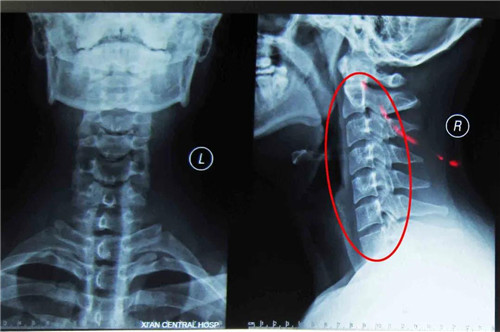

颈型颈椎病又称局部型颈椎病,X线片上没有椎间隙狭窄等明显的退行性改变,但可以有颈椎生理曲线改变、椎体间不稳定及轻度骨质增生等变化。不少反复落枕的病人即属于这种改变,是最早期的颈椎病,也是治疗最为有利的阶段。